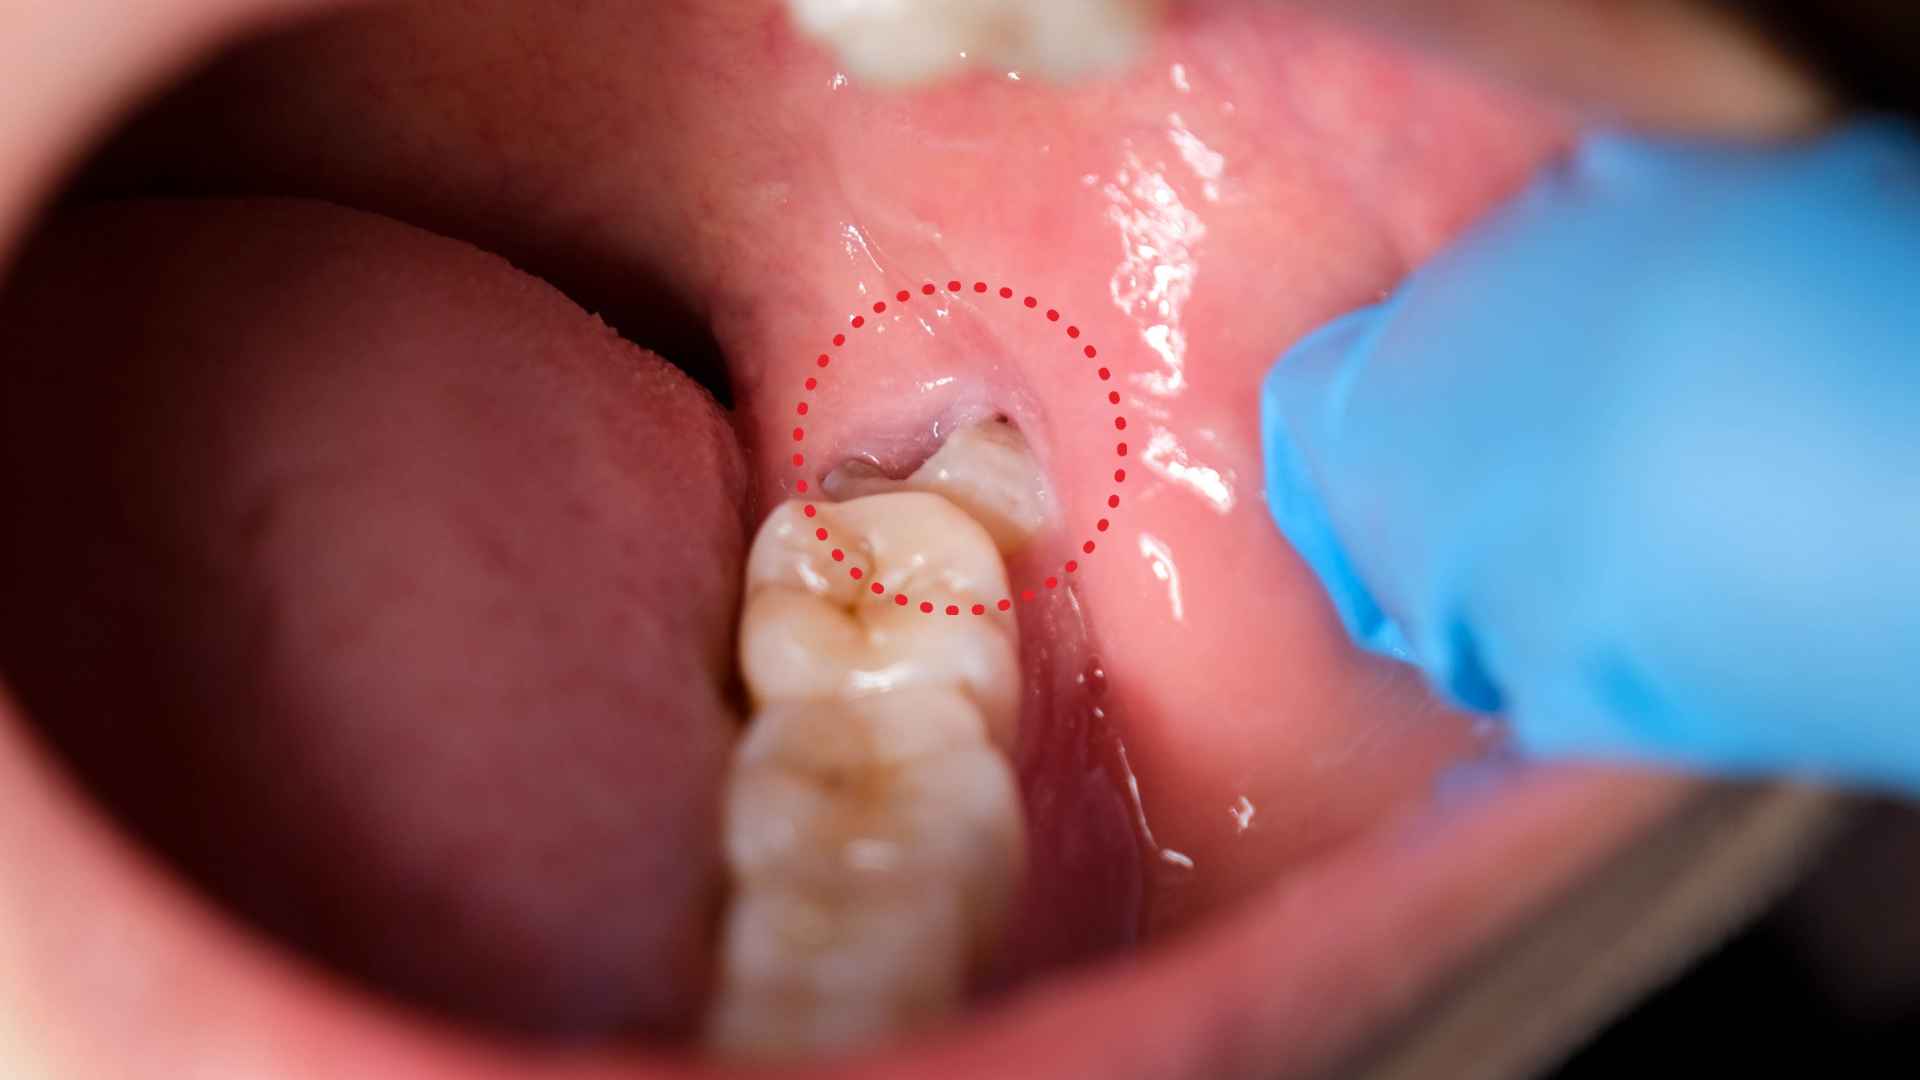

ที่ Time Dental Care เราเชี่ยวชาญด้านการผ่าตัดฟันคุดเพื่อช่วยจัดการความไม่สบายและป้องกันภาวะแทรกซ้อนที่เกี่ยวข้องกับฟันคุดที่มีปัญหา ฟันคุดเป็นฟันกรามซี่ที่สามที่มักขึ้นในวัยรุ่นปลายหรือผู้ใหญ่ตอนต้น หากฟันเหล่านี้ไม่มีพื้นที่เพียงพอในการขึ้น อาจทำให้เกิดความเจ็บปวด การติดเชื้อ และการเรียงตัวที่ผิดปกติของฟันอื่นๆ ทีมงานของเรามีทักษะและใช้เทคโนโลยีล่าสุดเพื่อให้การผ่าตัดเป็นไปอย่างปลอดภัยและมีประสิทธิภาพ ช่วยให้คุณฟื้นตัวได้อย่างรวดเร็วและสะดวกสบาย

• ลดความเสี่ยงของการติดเชื้อและโรคเหงือก

• บรรเทาอาการเจ็บปวดที่เกี่ยวข้องกับฟันคุดที่ติดหรือมีปัญหา